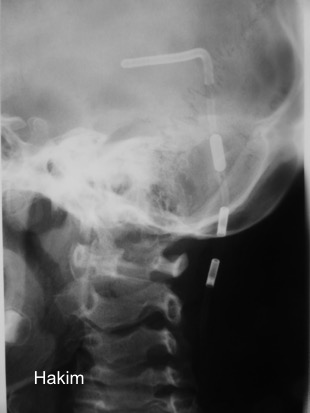

il existe un grand nombre de valves ; il n’est pas toujours aisé de les reconnaitre radiologiquement. voici la liste des plus courantes :

comment reconnaitre radiologiquement le type de valve ?